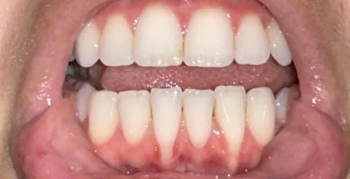

A Cone Beam Computed Tomography (CBCT) Scan is a high-tech 3D imaging system nga mas precise kaysa traditional X-rays. Makita sa dentist ang detailed structure sa imong bones, teeth, nerves, and soft tissues—perfect for: